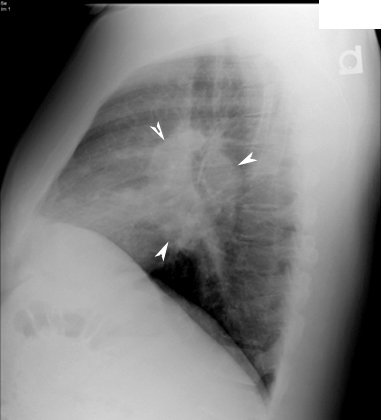

• Arrowheads point to hilar adenopathy.